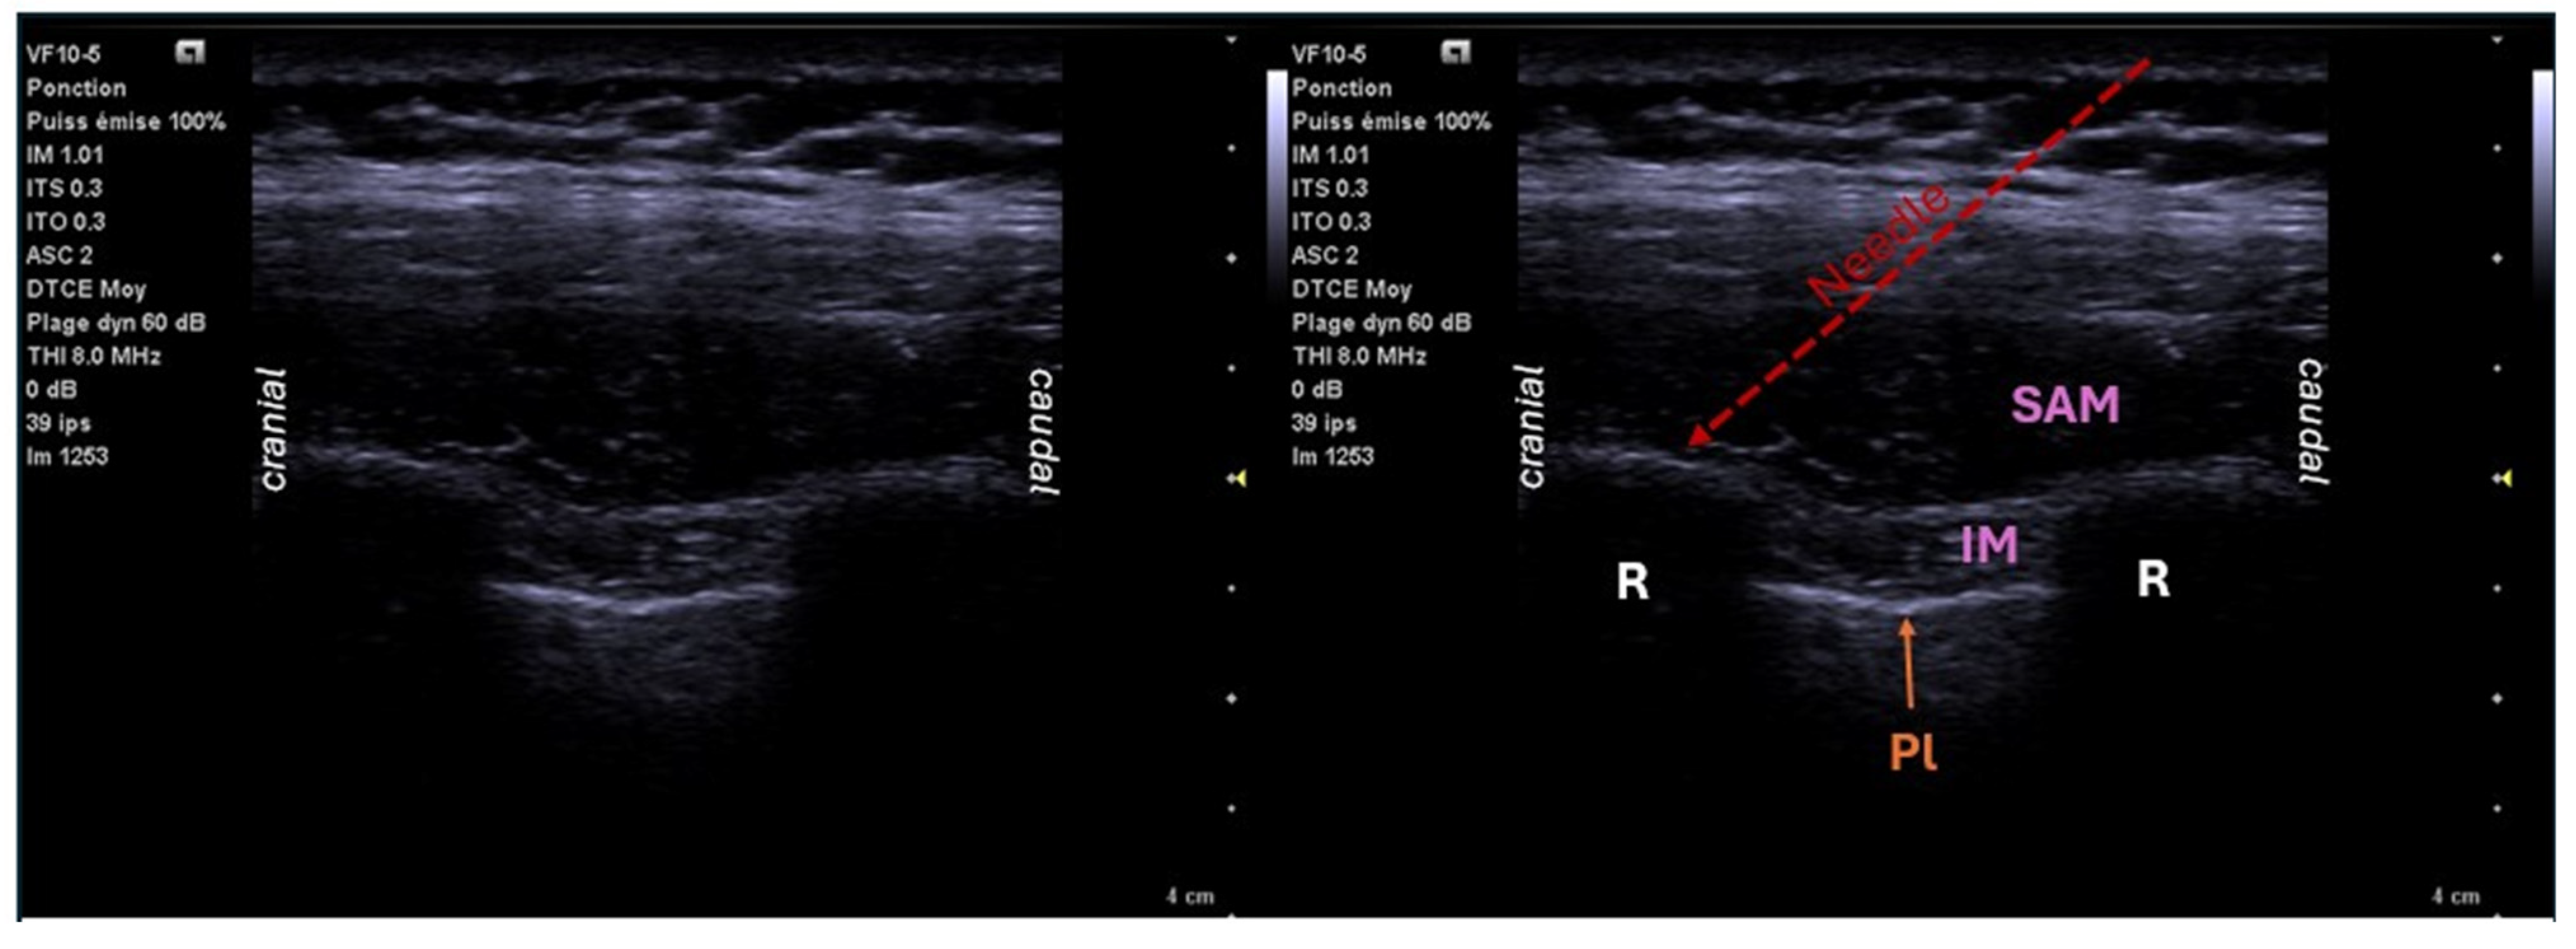

6.2. Erector Spinae Plane Block (ESPB)